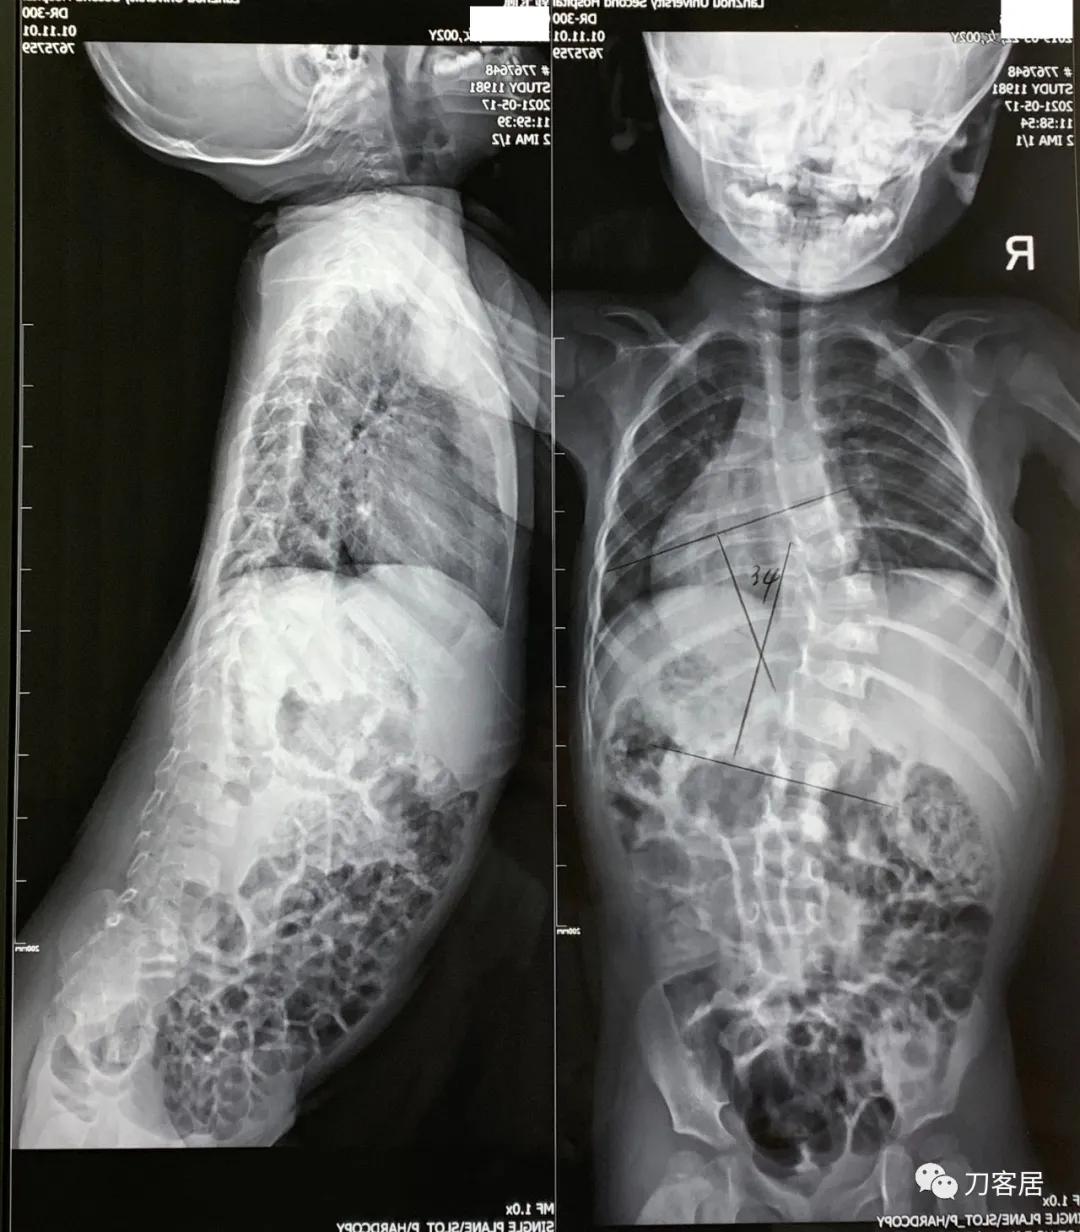

图10. 2021年5月17日Cobb角34度(开始支具治疗前拍摄)

这个患者的最后一张片,正位片子,可以看到肋骨头已经在开始变细,这是第一个迹象。第二个有向后凸发展的趋势,跟老的片子比,第三,顶椎区椎体的凸侧有凹陷,这些都是发生mutation的一个不好的迹象。所以这个病人,最后的结局是这个脊柱侧凸过渡到萎缩性脊柱侧凸。